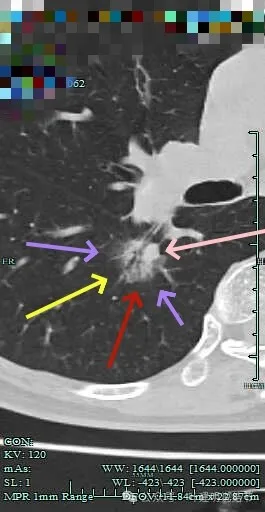

边缘有毛刺征!

沿支气管走行方向延伸,磨玻璃密度,且支气管内壁显得毛糙。

毛刺明显,轮廓清楚,灶内支气管扩张通气。

毛刺明显,灶内有实性成分出现。

毛刺征明显!!灶内密度杂乱。

实性成分较多,边缘毛刺。

毛刺征明显,而且是短毛刺且锐利。

毛刺。

靶重建显示混合密度,边缘毛糙,内部杂乱,灶内支气管通气且僵硬。

病灶影响到斜裂肺门部,边缘毛刺明显。灶内支气管僵硬。

密度杂乱,毛刺明显,支气管僵硬。